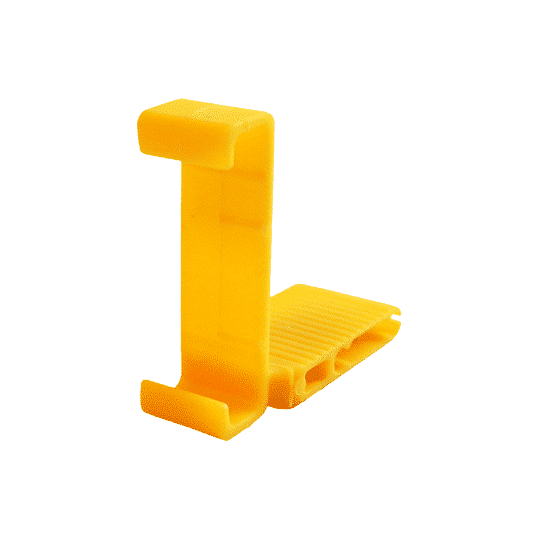

Sizes:

Size 1 blocks are for Size 1 child sensors (Approximately 20 mm x 30 mm)

Size 2 blocks are for Size 2 adult sensors (Approximately 26 mm x 36 mm)